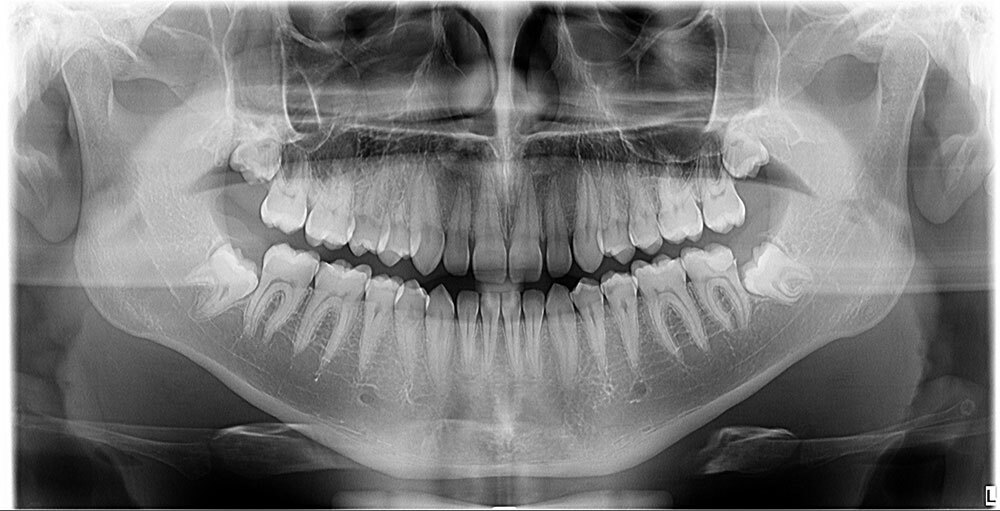

Naš rendgen centar ponosno koristi Dexis OP 3D Pro, uređaj koji omogućava potpuno digitalno i vrlo precizno snimanje.

Ovaj savremeni uređaj pruža jasne i detaljne slike koje olakšavaju dijagnostiku i planiranje terapije. Prednosti korišćenja Dexis OP 3D Pro uređaja su mnogobrojne:

Dexis OP 3D Pro donosi potpuno digitalno rešenje za ortopantomogram (OPG), telediogram, skanogram, bitewing, i 3D snimke vilice, čime pruža sveobuhvatnu podršku dijagnostici za različite stomatološke zahvate i analize.

| Ortopantomogram * | 2500 |